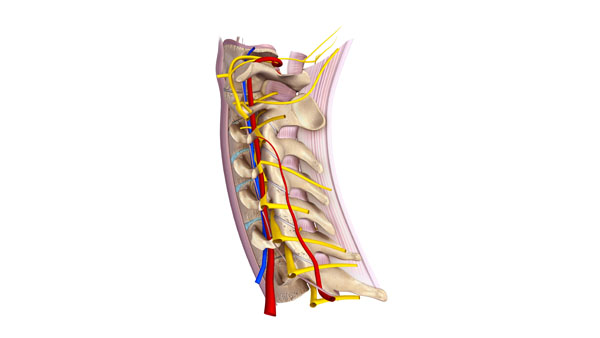

Spinal Ligaments

The provided image offers a detailed view of the ligaments associated with the spinal column. The ligaments are crucial structures that connect vertebrae to each other and contribute to the spine’s stability, while still allowing for a range of movements.

Key ligaments illustrated in the image include:

Anterior Longitudinal Ligament: This ligament runs along the anterior surfaces of the vertebral bodies, from the pelvic surface of the sacrum to the anterior tubercle of the atlas (C1). It restricts extension movements of the spine.

Posterior Longitudinal Ligament: This one is situated within the vertebral canal along the posterior surfaces of the vertebral bodies. It is narrower and weaker than the anterior longitudinal ligament and limits flexion of the spine.

Ligamentum Flavum: Also known as the yellow ligament due to its yellowish color from elastin fibers, it connects the laminae of adjacent vertebrae. It preserves the upright posture and assists with the spine’s elastic recoil after bending forward.

Interspinous Ligaments: These are found between the spinous processes of adjacent vertebrae. They help to limit flexion of the spine.

Supraspinous Ligament: This ligament connects the tips of the spinous processes from the seventh cervical vertebra (C7) down to the sacrum, and it resists flexion of the spine.

Intertransverse Ligaments: Located between the transverse processes of adjacent vertebrae, these ligaments restrict contralateral (opposite side) lateral flexion.

Together, these ligaments form a complex system that maintains the alignment of the vertebral column, allows for controlled movements, and protects the spinal cord and nerve roots. They work in concert with the muscles and tendons surrounding the spine to perform a wide range of motions and to provide stability against various forces that the spine encounters during daily activities.